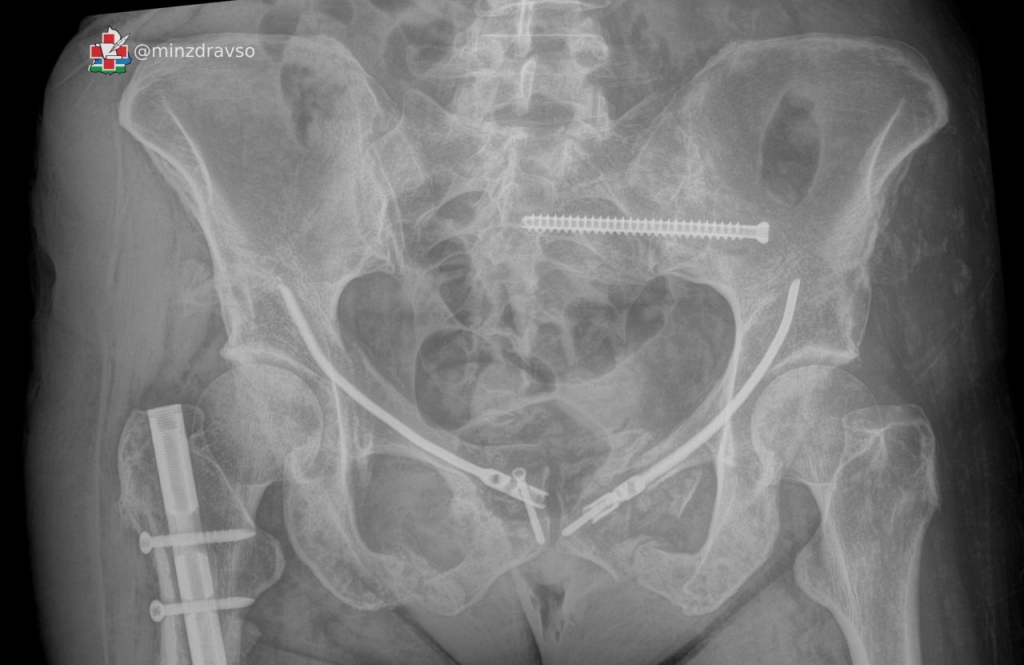

Специалисты нескольких отделений Верхнепышминской центральной городской клинической больницы общими усилиями спасли 50-летнюю женщину, которая выпала из окна четвёртого этажа. У пациентки были тяжёлые травмы таза и бедра, которые сопровождались массивным внутренним кровотечением. Борьба за её возвращение к нормальной жизни длилась более 120 дней, в течение которых врачи провели ей пять сложнейших оперативных вмешательств.

«Такое сочетание повреждений сопровождается массивным внутренним кровотечением с большой кровопотерей, напрямую угрожающей жизни. По жизненным показаниям пациентке была оперативно выполнена фиксация таза и бедра стержневым аппаратом внешней фиксации и проведено переливание крови», — рассказал заведующий травматологическим отделением Верхнепышминской ЦГКБ Андрей Репин.

В течение полутора месяцев пациентка находилась на интенсивной терапии в реанимационно-анестезиологическом отделении, из них 30 дней она была подключена к аппарату искусственной вентиляции лёгких. Верхнепышминские врачи и медсёстры круглосуточно боролись за её жизнь, проводили этапное оперативное лечение и многократные повторные гемотрансфузии — в общей сложности за это время ей перелили около 5 литров компонентов крови. Ситуация усугублялась большой массой тела женщины из-за ожирения II степени, которое негативно сказывалось на состоянии свердловчанки.

«Травма таза традиционно считается одной из самых сложных областей травматологии в связи с высокими рисками для жизни и здоровья пациентов и технической сложностью оперативных методов лечения. Чтобы восстановить форму повреждённых костей и стабилизировать переломы для правильного сращения и восстановления опорно-двигательной функции, потребовались пять сложнейших оперативных вмешательств на тазовом кольце и бедренной кости», — пояснил Андрей Репин.

По прошествии 120 дней, проведённых в больничных стенах, пациентка смогла встать на ноги. Во время пребывания в стационаре она избавилась от 30 лишних килограммов и в настоящее время уже благополучно вернулась домой.